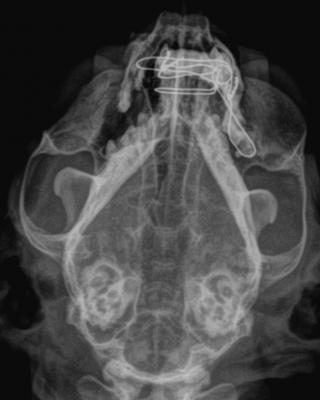

Komplikovaná fraktura čelisti

Vilibald byl přivezen na naší kliniku v podvečerních hodinách na pohotovostní ošetření po srážce s autem. Již na první pohled bylo patrné, že poranění obličeje jsou vážného rozsahu. Celkový zdravotní stav kocourka byl však v normě, proto jsme přistoupili k chirurgické rekonstrukci čelistí.

Dutina ústní byla kompletně zakrvácená, horní špičák čněl ven a při výdechu byla zřetelná epistaxe - výtok krve z nozder.

Klinickým a rtg vyšetřením byla zjištěna sagitální fraktura dolní čelisti, která bývá u koček poměrně častým nálezem. Trauma horní čelisti u Vilibalda však bylo mnohem horší - došlo k odlomení kusu horní čelisti včetně špičáku. Zlomenina tak pronikala až do dutiny nosní.

RTG snímek dutiny ústní po provedení chirurgické rekonstrukce čelisti.